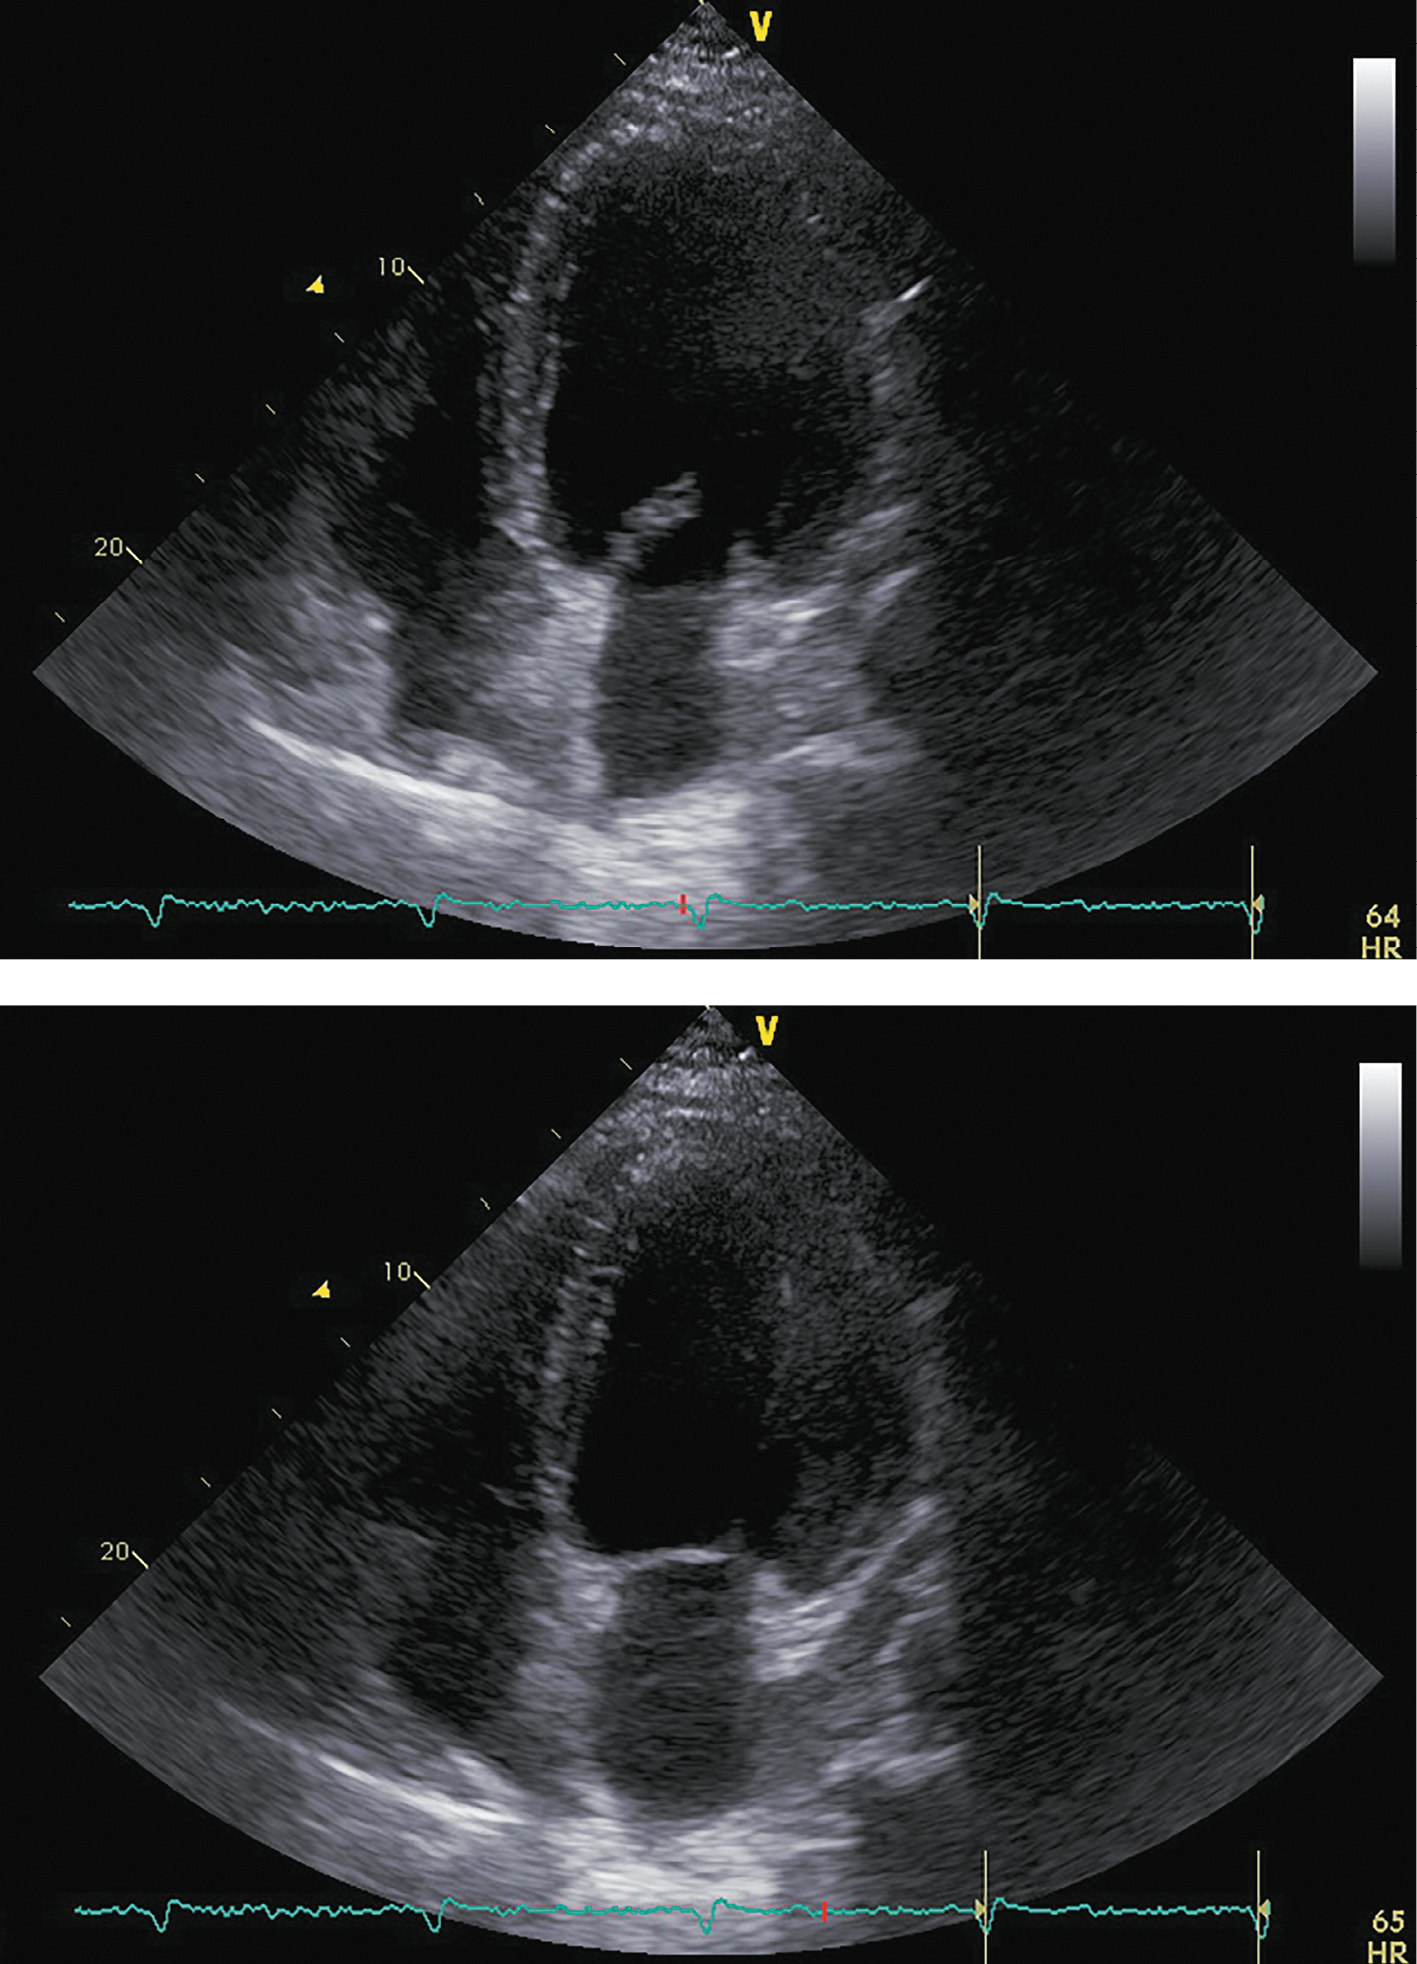

При госпитализации в октябре 2017 г. для проведения оперативного вмешательства было отмечено прогрессирование симптомов ХСН: выраженное снижение толерантности к нагрузкам с развитием одышки при минимальной физической активности, ночное ортопноэ, выраженные периферические отеки, физикальные симптомы легочного застоя (влажные хрипы в нижних отделах легких), гепатомегалия. Пациент сообщил, что получал предписанную терапию в полном объеме. На ЭХОКГ были отмечены выраженная дилатация левых камер сердца, признаки гипертрофии ЛЖ, диффузный гипокинез ЛЖ с выраженным снижением ФВ ЛЖ (19%), рестриктивная диастолическая дисфункция ЛЖ (рис. 4; табл. 2). Таким образом, несмотря на проводимую терапию, отмечено прогрессирование симптомов ХСН с дальнейшим снижением ФВ ЛЖ и развитием выраженной диастолической дисфункции. Потребовалась модификация терапии: назначение внутривенных диуретиков (фуросемид 80 мг) в течение 5 дней. После внутривенной диуретической терапии исчезли эпизоды ночного ортопноэ и физикальная симптоматика легочного застоя, существенно уменьшились периферические отеки. Постоянная пероральная терапия была модифицирована: добавлены БМКК, а также увеличены дозы пероральных диуретиков, ИАПФ, бетаАБ и кетоконазола (рис. 1). Операция была отложена на один месяц.

Рисунок 4. ЭХОКГ, 1 месяц до аденомэктомии.

Примечание: верхушечная 4-камерная позиция (сверху представлен кадр в диастолу, снизу — в систолу).

Таблица 2. ЭХОКГ-показатели, 1 месяц до аденомэктомии

|

Показатель |

Значение/индекс |

Объем левого предсердия |

135 мл/54 мл/м² |

Передне-задний размер левого желудочка |

7,20 см/2,89 см/м² |

Конечно-диастолический объем левого желудочка |

369 мл/148 мл/м² |

Конечно-систолический объем левого желудочка |

297 мл/119 мл/м² |

Локальная кинетика левого желудочка |

диффузный гипокинез |

Фракция выброса левого желудочка (усреднение по 4- и 2-камерным верхушечным позициям) |

19% |

Диастолическая функция левого желудочка |

градация III, рестриктивный тип |

Конечно-диастолическая площадь правого желудочка |

27 см²/10,8 см²/м² |

Конечно-систолическая площадь правого желудочка |

13,5 см²/5,4 см/м² |

Фракция систолического уменьшения площади |

50% |

Расчетное систолическое давление в легочной артерии |

50 мм рт.ст. |